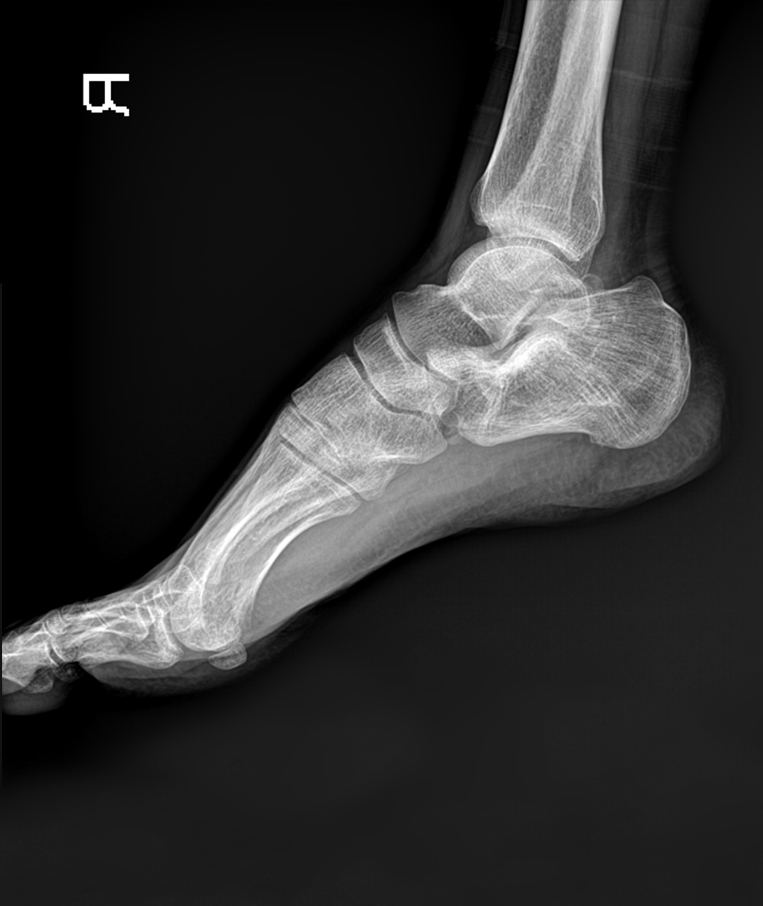

Clinical picture

臨床圖片